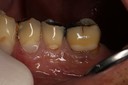

Mark Chun #18 pre-op

Mark Chun #19 caries removal

Mark Chun #18 prep